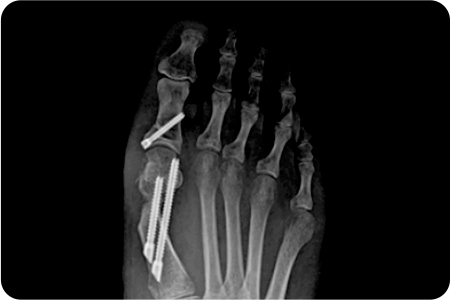

무지외반증 수술 적용사례

1

최소침습

무지외반증 수술

엄지발가락 부위에 약 2~3mm 크기의 작은

구멍을 만들고 특수한 미세 절삭 기구를 사용해

변형된 뼈를 절골하여 올바르게 교정합니다.